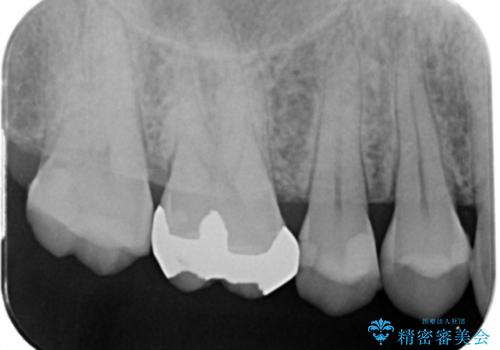

検査をしたところ、右上小臼歯に破折が見られ保存が難しい状況です。

抜歯を行い、咬合機能の回復を行いますが、咬合関係や非常に強い噛み合わせの問題をふまえ、咬合面をメタルにしたメタルボンドブリッジで治療を行うこととしました。

また噛み合わせが深くブリッジの強度が十分に確保できないことから、抜歯時に歯周外科を行うことで十分に安定したクラウン装着をできるような処置を行っています。